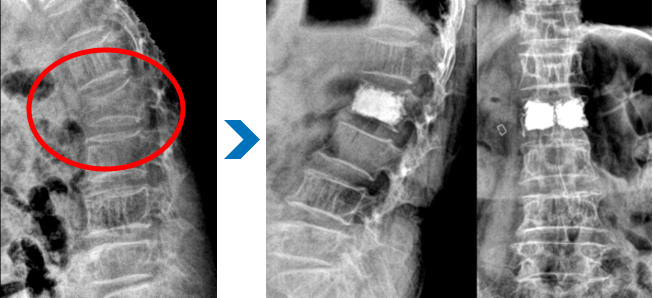

요통, 경추통, 방사통, 척추 골절, 척추 디스크, 척추관협착증, 척추전방전위증, 신경차단술, 척추신경성형술, 디스크고주파 감압술, 양방향 / 단일공 내시경하 수핵제거술, 척추 풍선복원술, 경추/요추 퇴행성질환 교정술 등